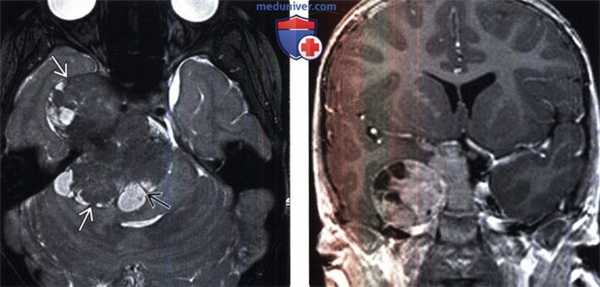

(Слева) При MPT Т2 ВИ в аксиальной проекции у этого же пациента определяется менингиома среднего отдела основания черепа; опухоль примерно изоинтенсивна по сравнению с серым веществом, между опухолью и смещенной височной долей видна ликворная/сосудистая щель. Небольшой компонент опухоли в задней черепной ямке деформирует мост.

(Справа) При корональной МРТ Т1 ВИ FS с КУ на медиальной поверхности пирамиды височной кости определяется экстрааксиальное объемное образование, прорастающее во внутренний слуховой проход и яремное отверстие. Виден гиперостоз верхней стенки внутреннего слухового прохода.

(Слева) При MPT Т1ВИ с КУ в сагиттальной проекции у переднего края большого затылочного отверстия определяется глобулярное объемное образование, смещающее продолговатый мозг кзади. Наличие фиксированного к твердой мозговой оболочке широкого основания свидетельствует в пользу менингиомы, а не какого-либо другого новообразования большого затылочного отверстия, например, шванномы.

(Справа) При МРТ Т1ВИ с КУ в аксиальной проекции определяется менингиома переднего края большого затылочного отверстия, лежащая медиальнее левой позвоночной артерии. Учитывая наличие в основании черепа большого количества критически важных сосудистых и нервных структур, резекция даже небольших новообразований может быть затруднена.